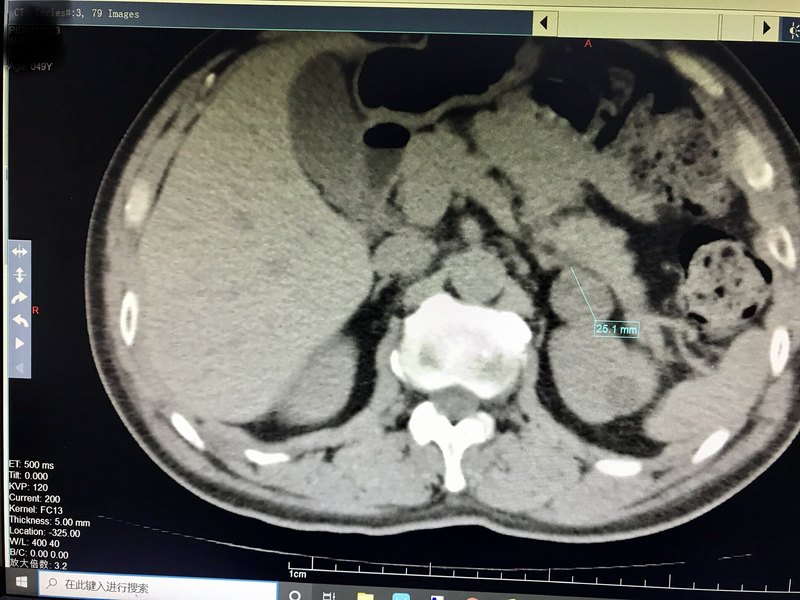

- 腎上腺包塊需謹(jǐn)慎?。?!

目前住院的一例患者,7年前腎上腺包塊2.5cm,隨后定期復(fù)查。1復(fù)查需要做ct,擔(dān)心輻射,近幾年未再復(fù)查,2另外由于腎上腺位置很深,體檢時(shí)常規(guī)b超很難發(fā)現(xiàn),3包塊就算惡變,也沒有什么癥狀,4腎上腺包塊如果發(fā)生惡變,惡性程度很高,堪比胰腺癌,預(yù)后很差。 這是患者目前的ct,希望患者明天術(shù)后的病理結(jié)果是良性吧。再次提醒,并給大家做個(gè)科普吧,1腎上腺包塊一定要定期復(fù)查,怎么也得一年一次,2有可能復(fù)查的時(shí)候沒事,但過幾年一疏忽就忘了復(fù)查了,這時(shí)候腎上腺包塊有可能發(fā)生惡變,3如果年齡尚可,身體狀況好,腎上腺包塊已經(jīng)有2公分左右,也可以微創(chuàng)手術(shù)切除。由于只切除包塊,所以創(chuàng)傷很小,手術(shù)給患者帶來的是利大于弊! 今天腹腔鏡微創(chuàng)手術(shù)切除了腫瘤,術(shù)中出血20毫升,手術(shù)時(shí)間30分鐘,非常順利。 等待術(shù)后的病理結(jié)果吧。